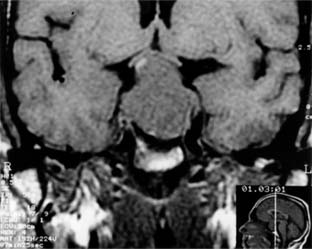

The anterior lobe of the pituitary gland is the site of origin of pituitary tumors (Figure 14-26). Symptoms and signs include loss of vision, field changes, pituitary dysfunction, extraocular nerve palsies, and evidence on CT scan or MRI of sellar and suprasellar tumor.

Figure 14-26

Figure 14-26: Coronal MRI showing large pituitary adenoma elevating and distorting the optic chiasm.

Combination therapy with radiation and surgery has been challenged by medical treatment with bromocriptine, which has been effective not only in tumors associated with galactorrhea but also in some null cell (or endocrinologically inactive) tumors. Visual loss or endocrine dysfunction is an indication for treatment. Visual acuity and visual fields may improve dramatically after pressure has been removed from the chiasm. The initial appearance of the optic nerve head does not predict the ultimate visual outcome.